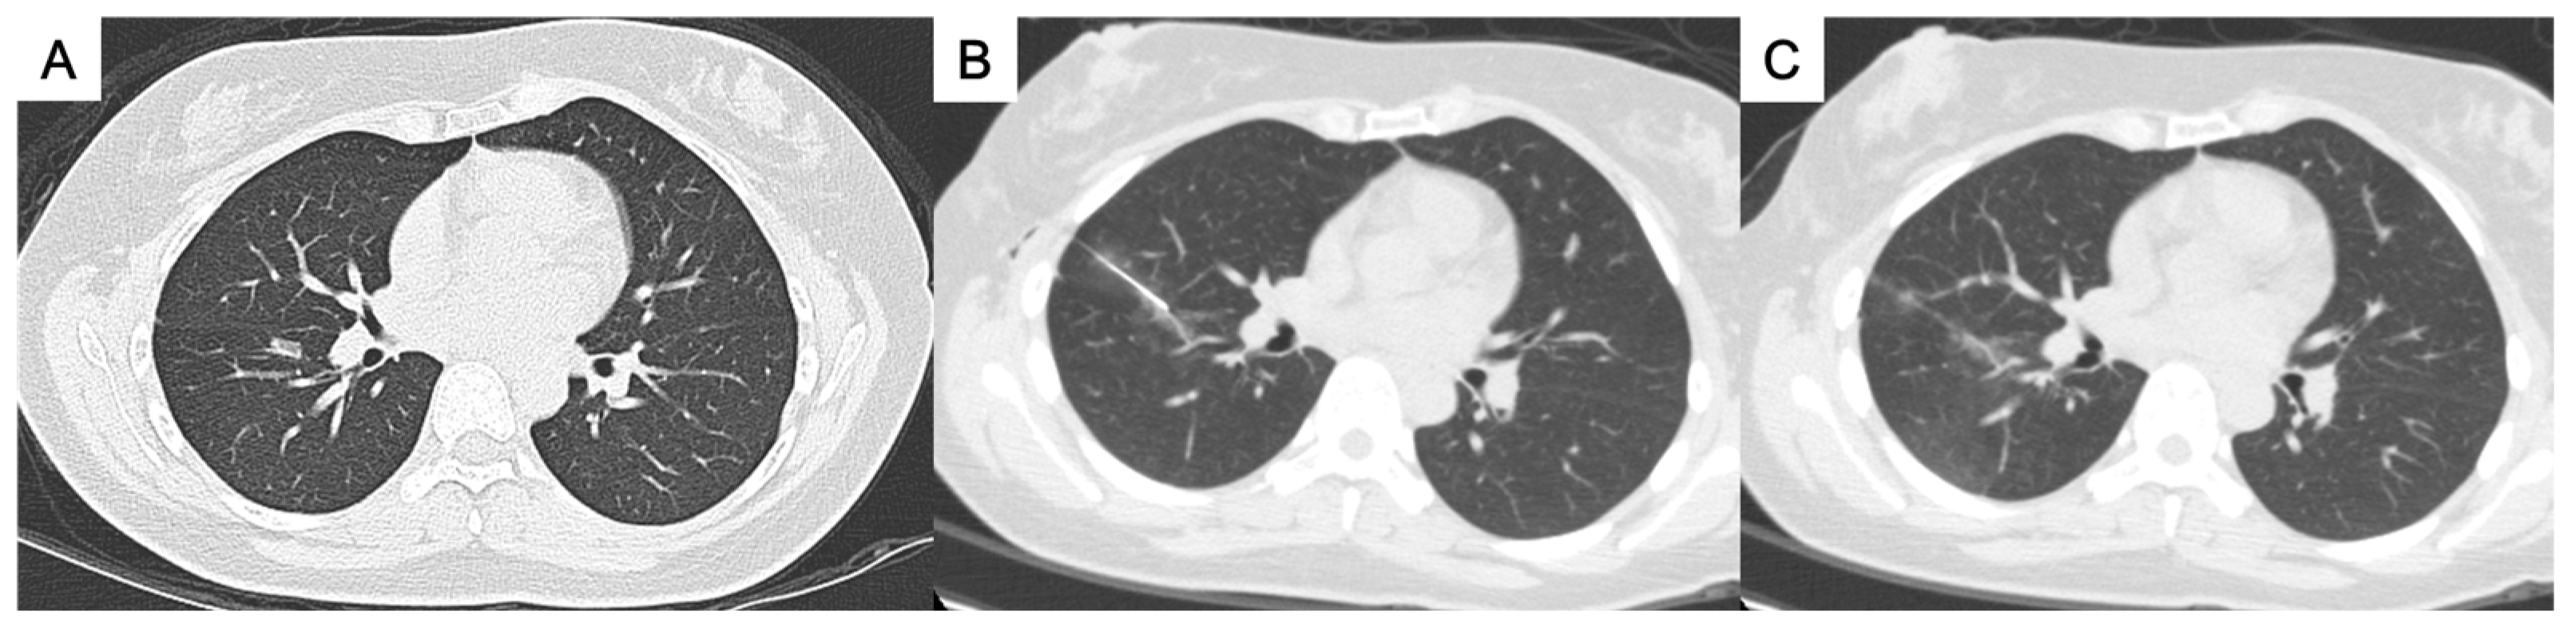

Figure 2. (A) A ground-glass nodule in the right lower lobe near the interlobar fissure. (B, C) A transfissural puncture was performed, followed by patent blue dye injection into the subpleural area near the nodule. The pathological result was adenocarcinoma.

• For the perifissural nodules (Figure 1), we introduced the needle by the shortest way from the chest wall to the nodule and injected the PBD in the subpleural area. There is an alternative transfissural approach (Figure 2) to avoid pulmonary vessels, scapula, and ribs, with the dye retention in the subpleural area.

• Perifissural nodules: nodules close to the interlobar fissure (Figure 1 and Figure 2) ;